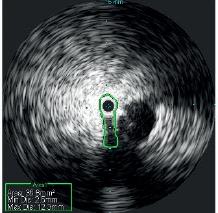

The use of covered self-expanding stents and percutaneous balloon angioand venoplasty formalized the iatrogenic arteriovenous fistula. Post-intervention IVUS using the Reconnaissance .018 OTW IVUS catheter verified appropriate luminal gain and aided identification of incomplete venous valvular disruption in the foot ( see Figure 3 ). Target areas of venous outflow were addressed with repeated venoplasty. At one-month follow-up, the

Evaluation of the central veins in the pelvis with venogram revealed no focal iliac vein stenosis or filling defect, and there were no cross-pelvic or lumbar collaterals noted. IVUS with the Visions .035 system was performed, identifying a severe cranial external iliac vein (EIV) stenosis (73%), compared to the normal suprainguinal caudal EIV, due to a non-thrombotic iliac vein lesion (NIVL). Normal suprainguinal caudal EIV and severe cranial external iliac vein stenosis (see Figures 4 and 5)

Post-angioplasty and stent, there was no